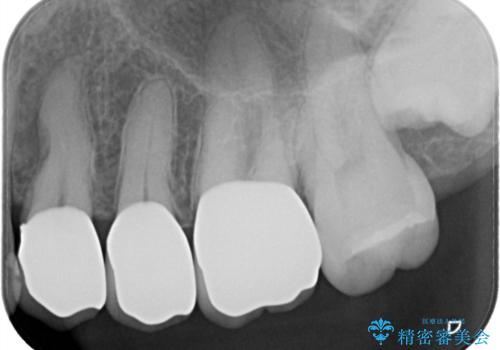

- 定期健診にて虫歯が見つかった患者さんです。県外からお越しいただいている事もあり、かなりお久しぶりの来院でした。歯と歯の間のところと銀歯の下が虫歯になっていました。被せ物はオールセラミッククラウンで治療しました。

銀歯を外すとかなり大きな虫歯になっていました。幸いぎりぎりのところで神経まで虫歯は広がっていなかったため、症状が出ない事を確認した後、オールセラミッククラウンで治療しました。虫歯除去後、残っている歯質が少なかったため、破折抵抗を考慮し部分的な被せ物ではなくクラウンを選択しました。

※被せ物では歯と被せ物の適合がとても大切になります。適合が悪い被せもの(歯と被せものの間に隙間がある)を入れるとそこに汚れが溜り虫歯の原因となります。当院では精度が高い被せものを追求するため、サージテル(拡大鏡)や型取りの材料にシリコン材を使用しています。